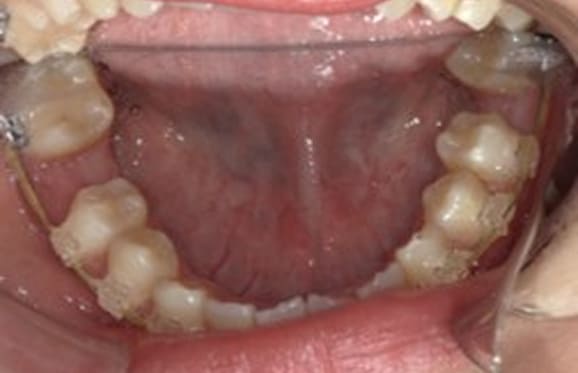

● C4を超え歯根までの虫歯を抜歯、親知らずを利用して歯並び全体を整えた症例

藤沢デンタルオフィスの虫歯や破折で抜歯後の部分矯正